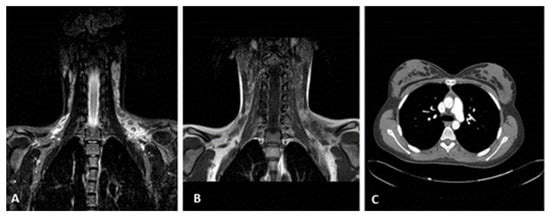

MRI (cervical/supraclavicular region): multiple hypoechoic, rounded lymph nodes (Figure 3A,B).

Radiological findings: (A,B) MRI in the cervical and supraclavicular areas, mainly on the left; multiple lymph nodes are observed that converge in some areas. Some of them, being rounded off, show an intermediate signal on the T1 sequence and a low signal on the STIR, while on the diffusion sequences, they show a restriction. The perilymph node tissue shows an intense high signal on fat suppression sequences to the left, while on T1 sequences, it shows inhomogeneous high signal and increased diffusion. (C) CT scan of the thorax and abdomen: no obvious pathological findings; a number of lymph nodes up to 7 mm in diameter are observed paraaortically and in the mesentery. Central tracheobronchial tree free, no pathologically sized lymph nodes in the hilar and mediastinum.